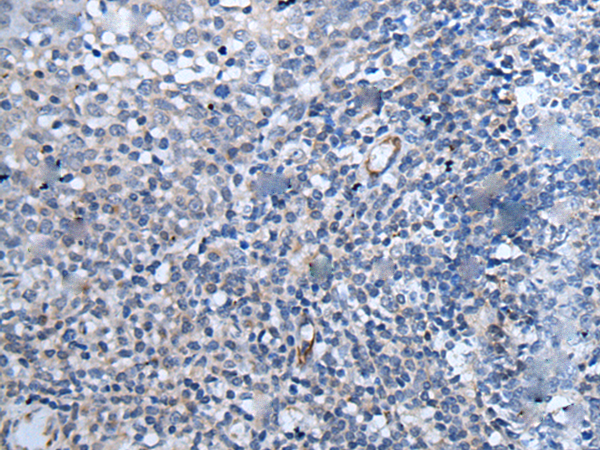

分类: 科研抗体货号: P12831别名: RINZF应用: WB,IHC反应种属: Human

分类: 科研抗体货号: P12810别名: PSA; SGPA; ZNF912应用: WB,IHC反应种属: Human, Mouse, Rat

分类: 科研抗体货号: P12830别名: F3; GP135; MYPCN应用: WB,IHC反应种属: Human, Mouse, Rat

分类: 科研抗体货号: P12808别名: OX; PPOX; NRCLP1应用: IHC反应种属: Human, Mouse, Rat

分类: 科研抗体货号: P12828别名: SVCT1; YSPL3; SLC23A2应用: IHC反应种属: Human

分类: 科研抗体货号: P12788别名: CNM3; MRF4; myf-6; bHLHc4应用: IHC反应种属: Human, Mouse, Rat

分类: 科研抗体货号: P12827别名: DIPAS; TAF4B; PAPPAS; TAF2C2; PAPPAAS; PAPPA-AS; TAFII105; NCRNA00156应用: IHC反应种属: Human